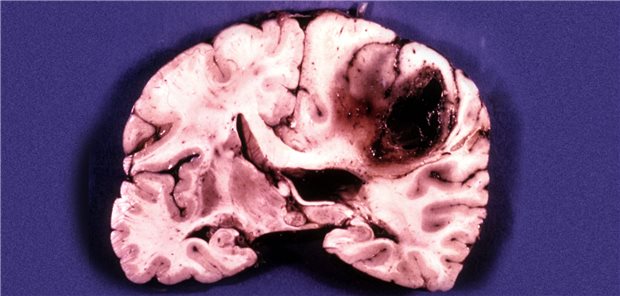

Jetzt ist geklärt, wie sich Glioblastome im Hirn ausbreiten: Krebszellen bewegen sich „nach dem gleichen Muster durch das Gehirn wie Raubtiere auf der Suche nach Beute durch ihr Revier“, sagt ein Forscher.